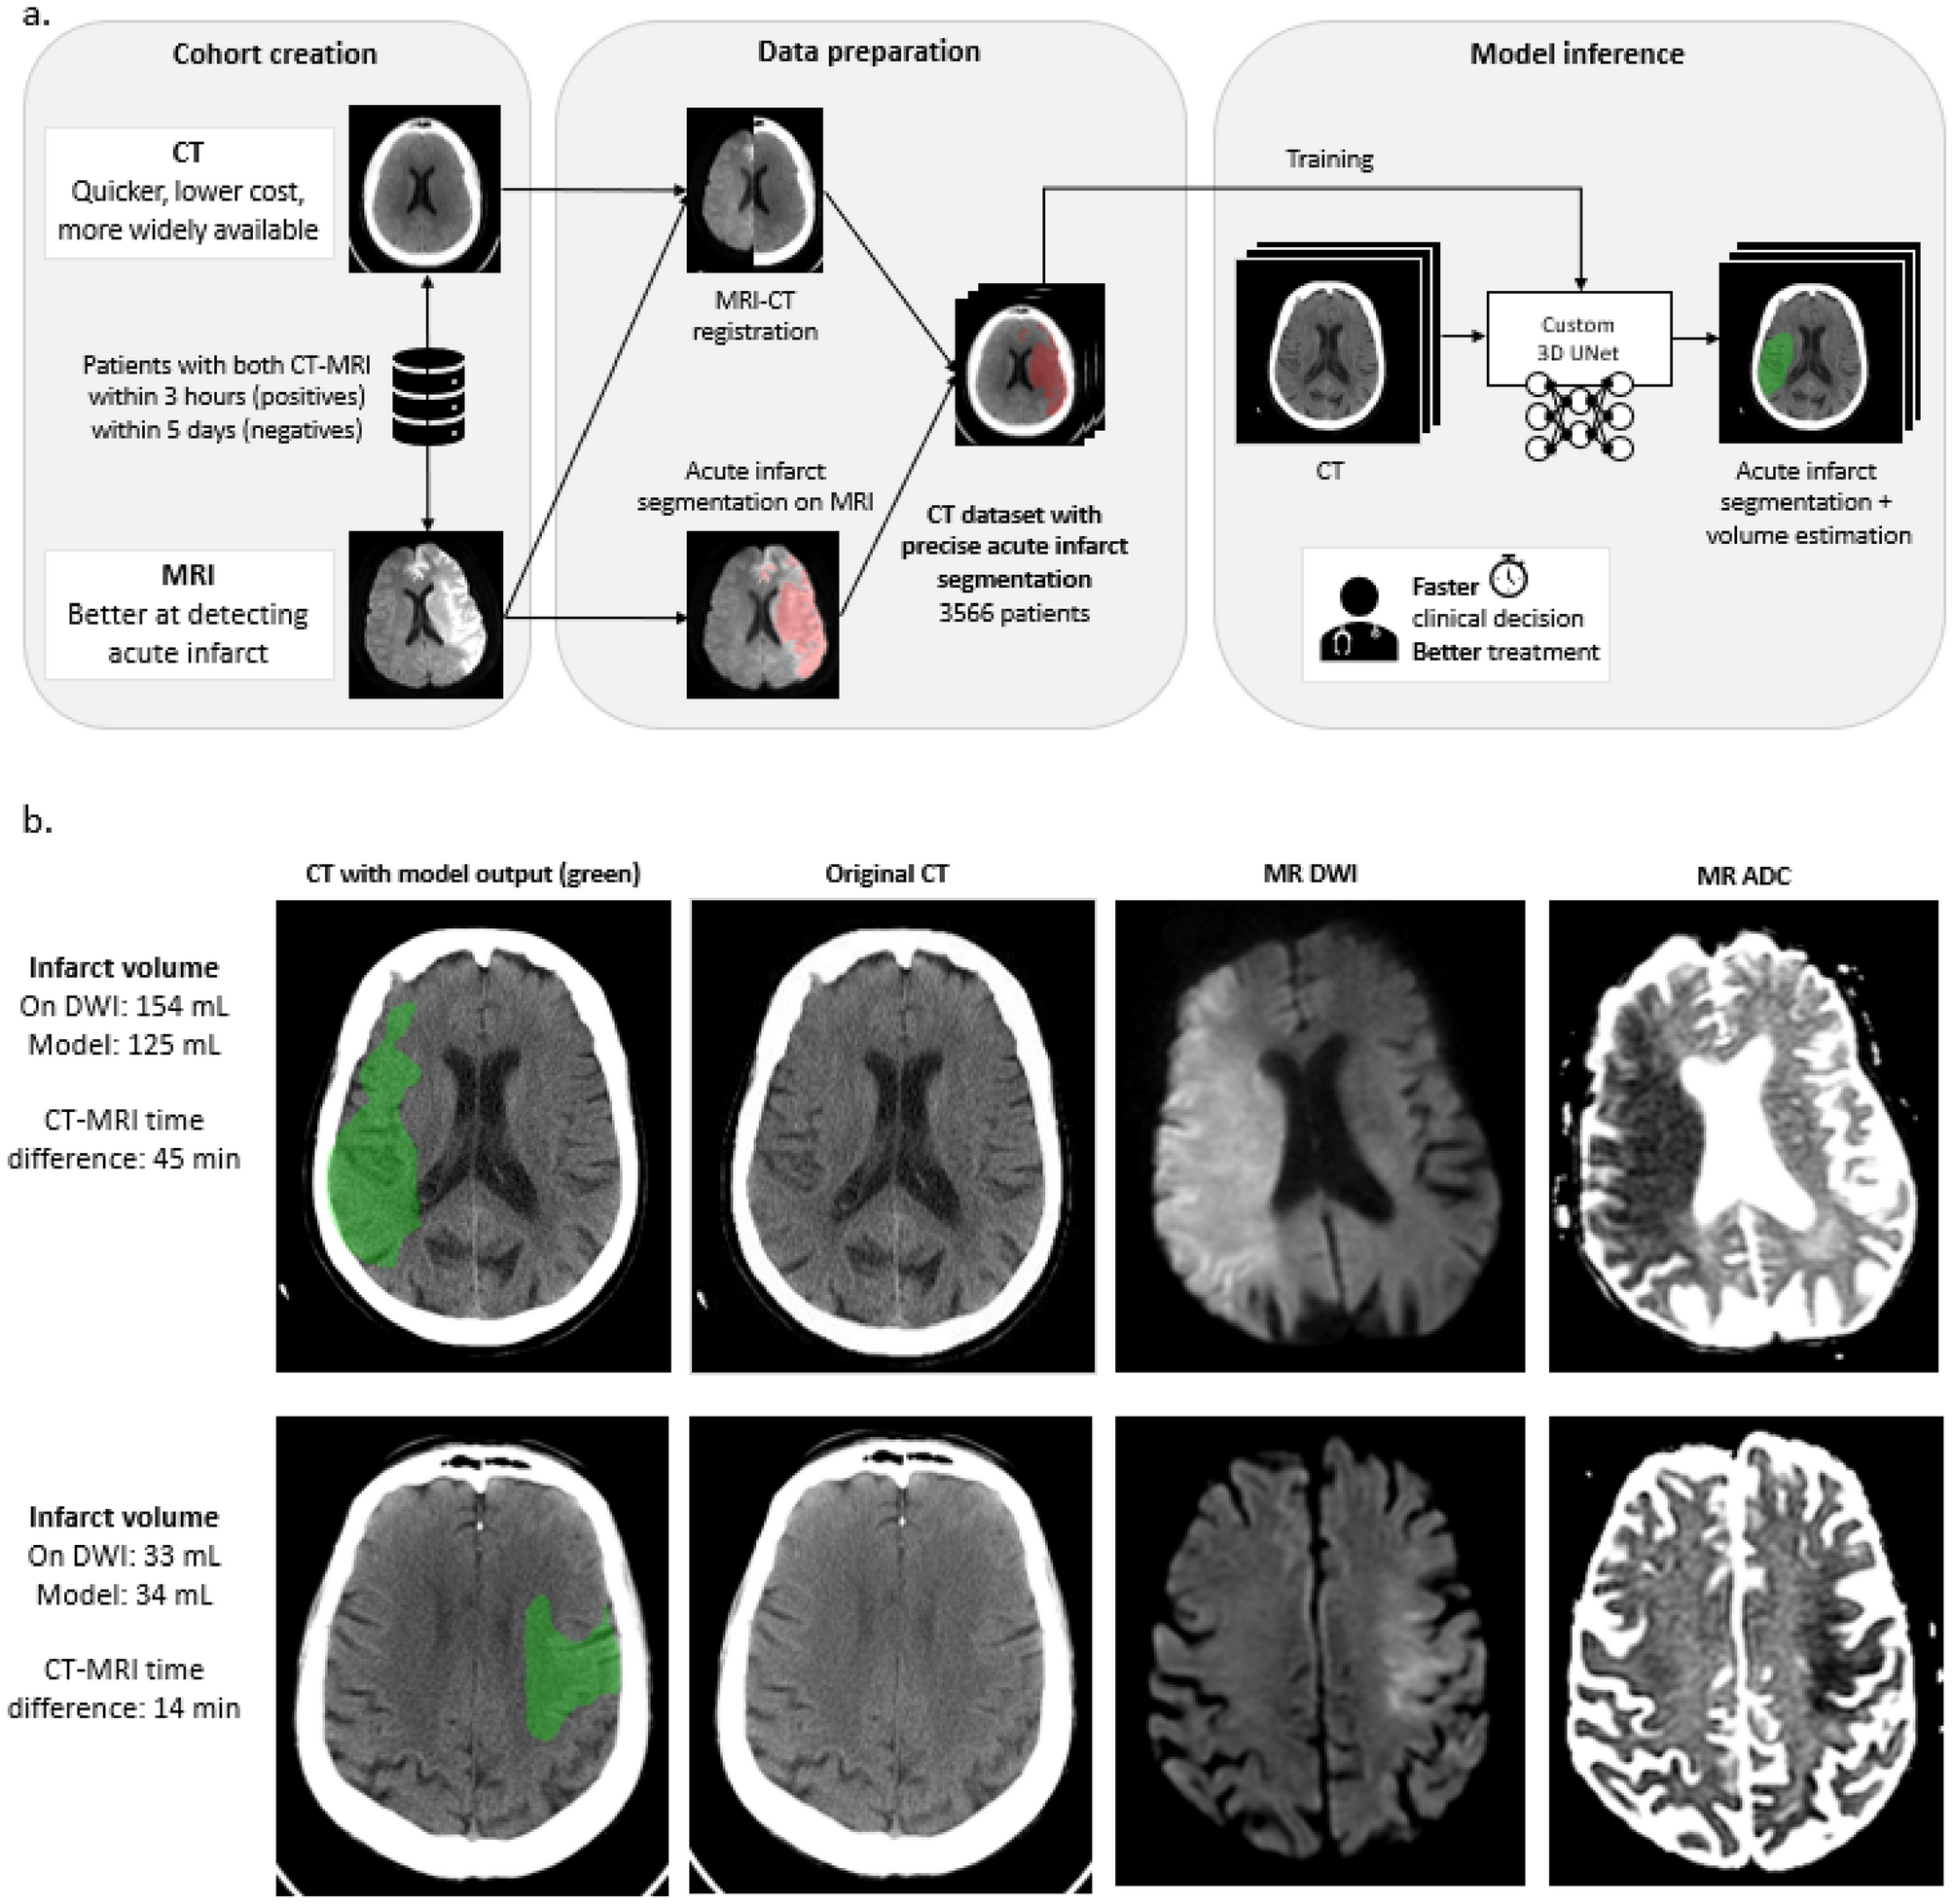

Figure 3

From: Head CT deep learning model is highly accurate for early infarct estimation

(a) Schematic representation of model development steps from cohort creation and data preparation to model inference training. (b) Examples of infarcts not detected by each of the three expert neuroradiologists, but accurately detected and delineated by the model.